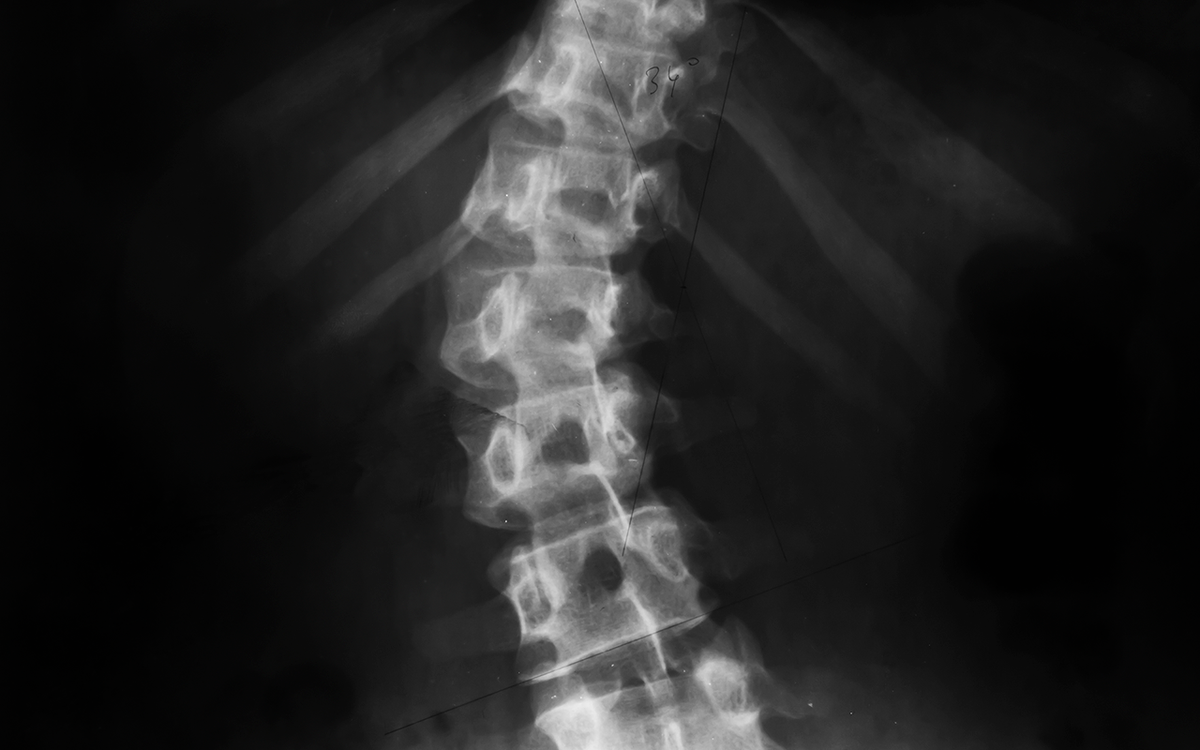

Röntgenfoto scoliose

Dat kinderen met het 22q11-syndroom mogelijk vaker een scoliose ontwikkelen dan de algemene bevolking, was al duidelijk. Hoe vaak precies wist men niet. Jelle Homans promoveerde donderdag 23 januari op onderzoek hiernaar. Hij toonde aan dat  48-49% van deze kinderen een scoliose krijgt. “Daarnaast hebben we laten zien dat het scoliose-type van deze kinderen niet afwijkt van mensen met scoliose zonder het syndroom. Bij sommige ziekten – zoals spierziekten – is ook het risico op scoliose groter, maar dat is een ander soort scoliose dan de idiopathische scoliose. Dat wilden we bij het 22q11-ook onderzoeken.”